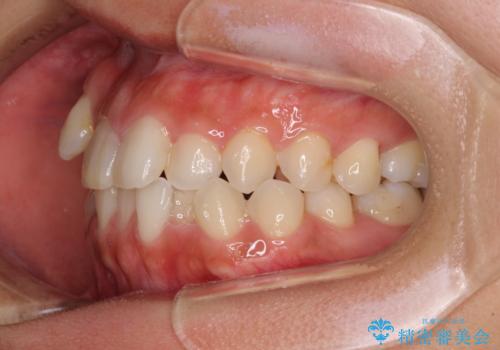

裏側装置での矯正治療は、上顎前歯の正中のズレをまっすぐに改善することが難しいのですが、きれいに整えることができました。

補助装置を用いて抜歯したスペースを速やかに閉じたことで、短期間での治療となりました。